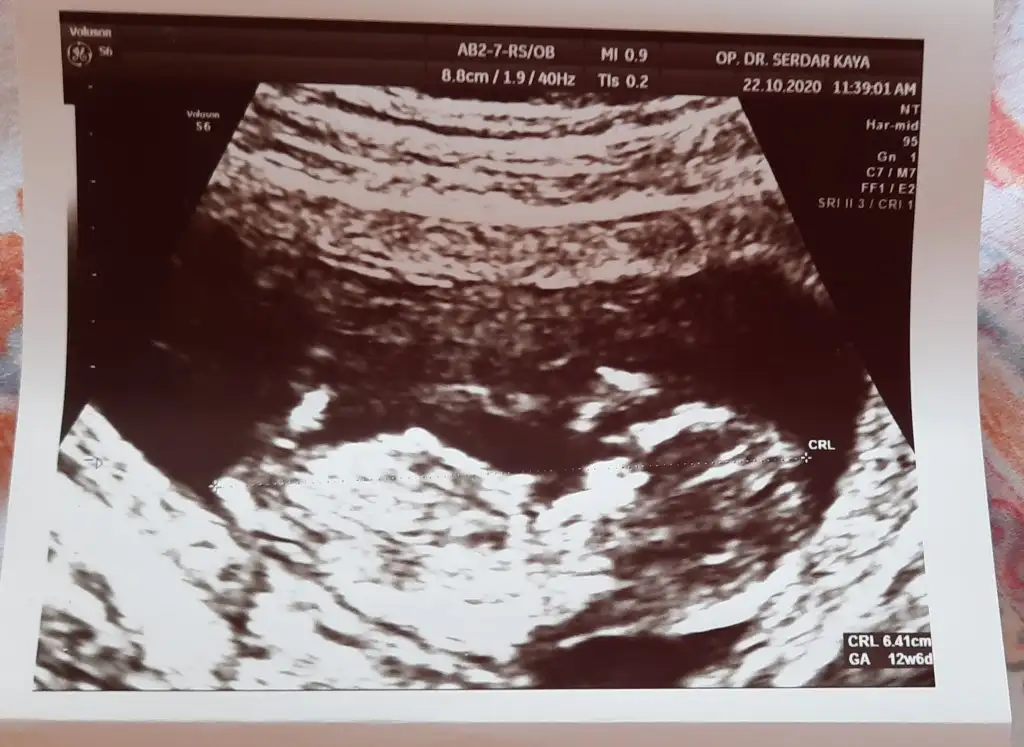

Merhaba Ikra meyra canım, bir tahmin alabilir miyim ben de 13+2 olduk.

Eklentiler

• 20201021_114201.webp

23,3 KB · Görüntüleme: 67

• 20201021_114209.webp

23,7 KB · Görüntüleme: 55

• 20201021_114216.webp

18,4 KB · Görüntüleme: 84